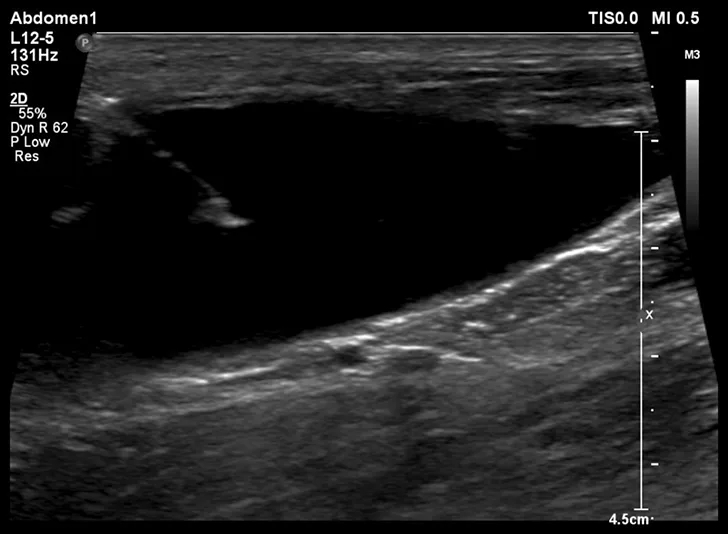

After cystocentesis, a small amount of gas may be introduced into the urinary bladder iatrogenically but is typically of no clinical consequence (Figure 3). Evidence of this can be seen on ultrasonography after the procedure is completed and appears as horizontally oriented, parallel hyperechoic lines reverberating off the introduced gas.

Reverberation artifact from free gas that was iatrogenically left in the urinary bladder after cystocentesis, noted by the parallel, horizontally oriented hyperechoic lines extending into the urinary bladder (arrow). This is not considered a complication but may be seen following the procedure.